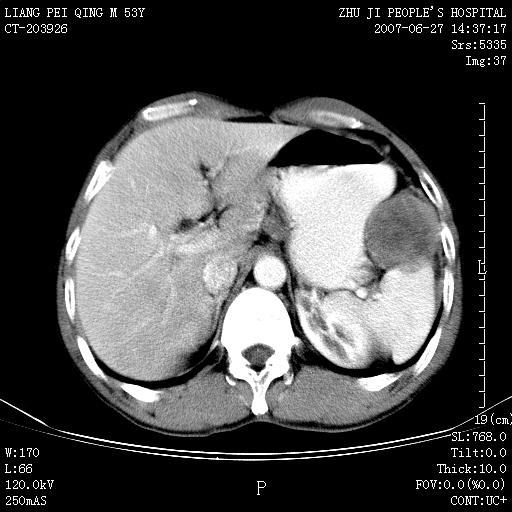

以下是引用余辉在2007-6-27 18:46:00的发言:[br]病灶多发,内可见大片状低密度区,病灶病灶等密度区轻度强化,动脉期后期病灶低密度区与高密度区对度增加,考虑1淋巴瘤2转移瘤3血管内皮细胞瘤(不知有否静脉期及延迟期扫描)

以下是引用zzzzhhhhaaaannnn在2007-6-27 20:44:00的发言:[br]脾脏 肋骨转移可能性大,下腔静脉内有癌栓

以下是引用狙击手在2007-6-28 10:35:00的发言:[br]1:定位:来源于脾脏。2:强化:强化,但不均匀。3:下腔静脉癌栓?下腔静脉充填不均匀与增强时间有关,延时即可明确。4:肋骨破坏?看起来并不确切。综上考虑几个最常见诊断:1;淋巴管瘤;2;血管内皮肉瘤(高度恶性,早期即可转移,常见肝,肺,骨)3;转移瘤(无特征性,只有肝或其它腹腔脏器有类似病变时,才可提示之)